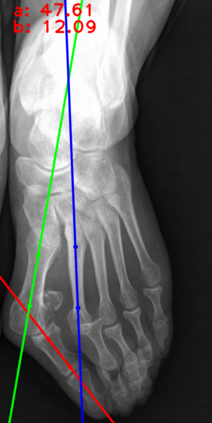

Angular measurements is essential to make a resonable treatment for Hallux valgus (HV), a common forefoot deformity. However, it still depends on manual labeling and measurement, which is time-consuming and sometimes unreliable. Automating this process is a thing of concern. However, it lack of dataset and the keypoints based method which made a great success in pose estimation is not suitable for this field.To solve the problems, we made a dataset and developed an algorithm based on deep learning and linear regression. It shows great fitting ability to the ground truth.